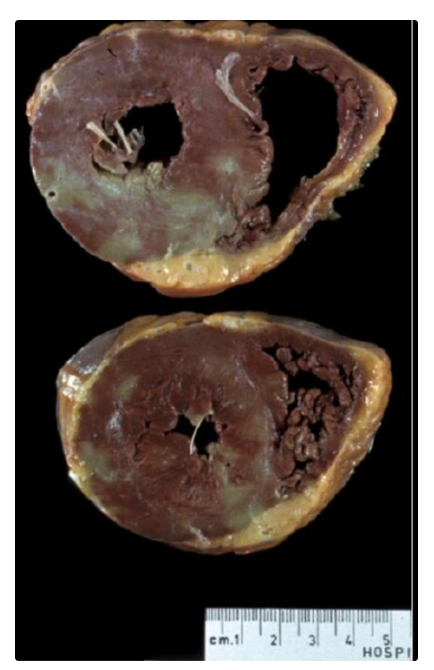

Mixoma

Rabdomioma